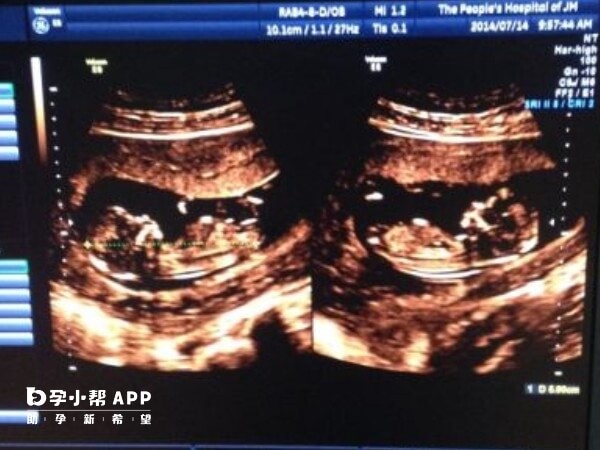

双胞胎大排畸检查主要针对两个胎儿的结构和发育情况进行全面筛查,如果当检查过程中发现其中一个胎儿有出现问题,那么可通过以下方法进行进一步处理。

双胞胎大排畸一个有问题,同时若畸形严重且无法治愈,可考虑选择性减胎。手术需在超声引导下进行,确保准确终止异常胎儿,同时保护正常胎儿。减胎后需密切监测孕妇身体状况及剩余胎儿发育情况。